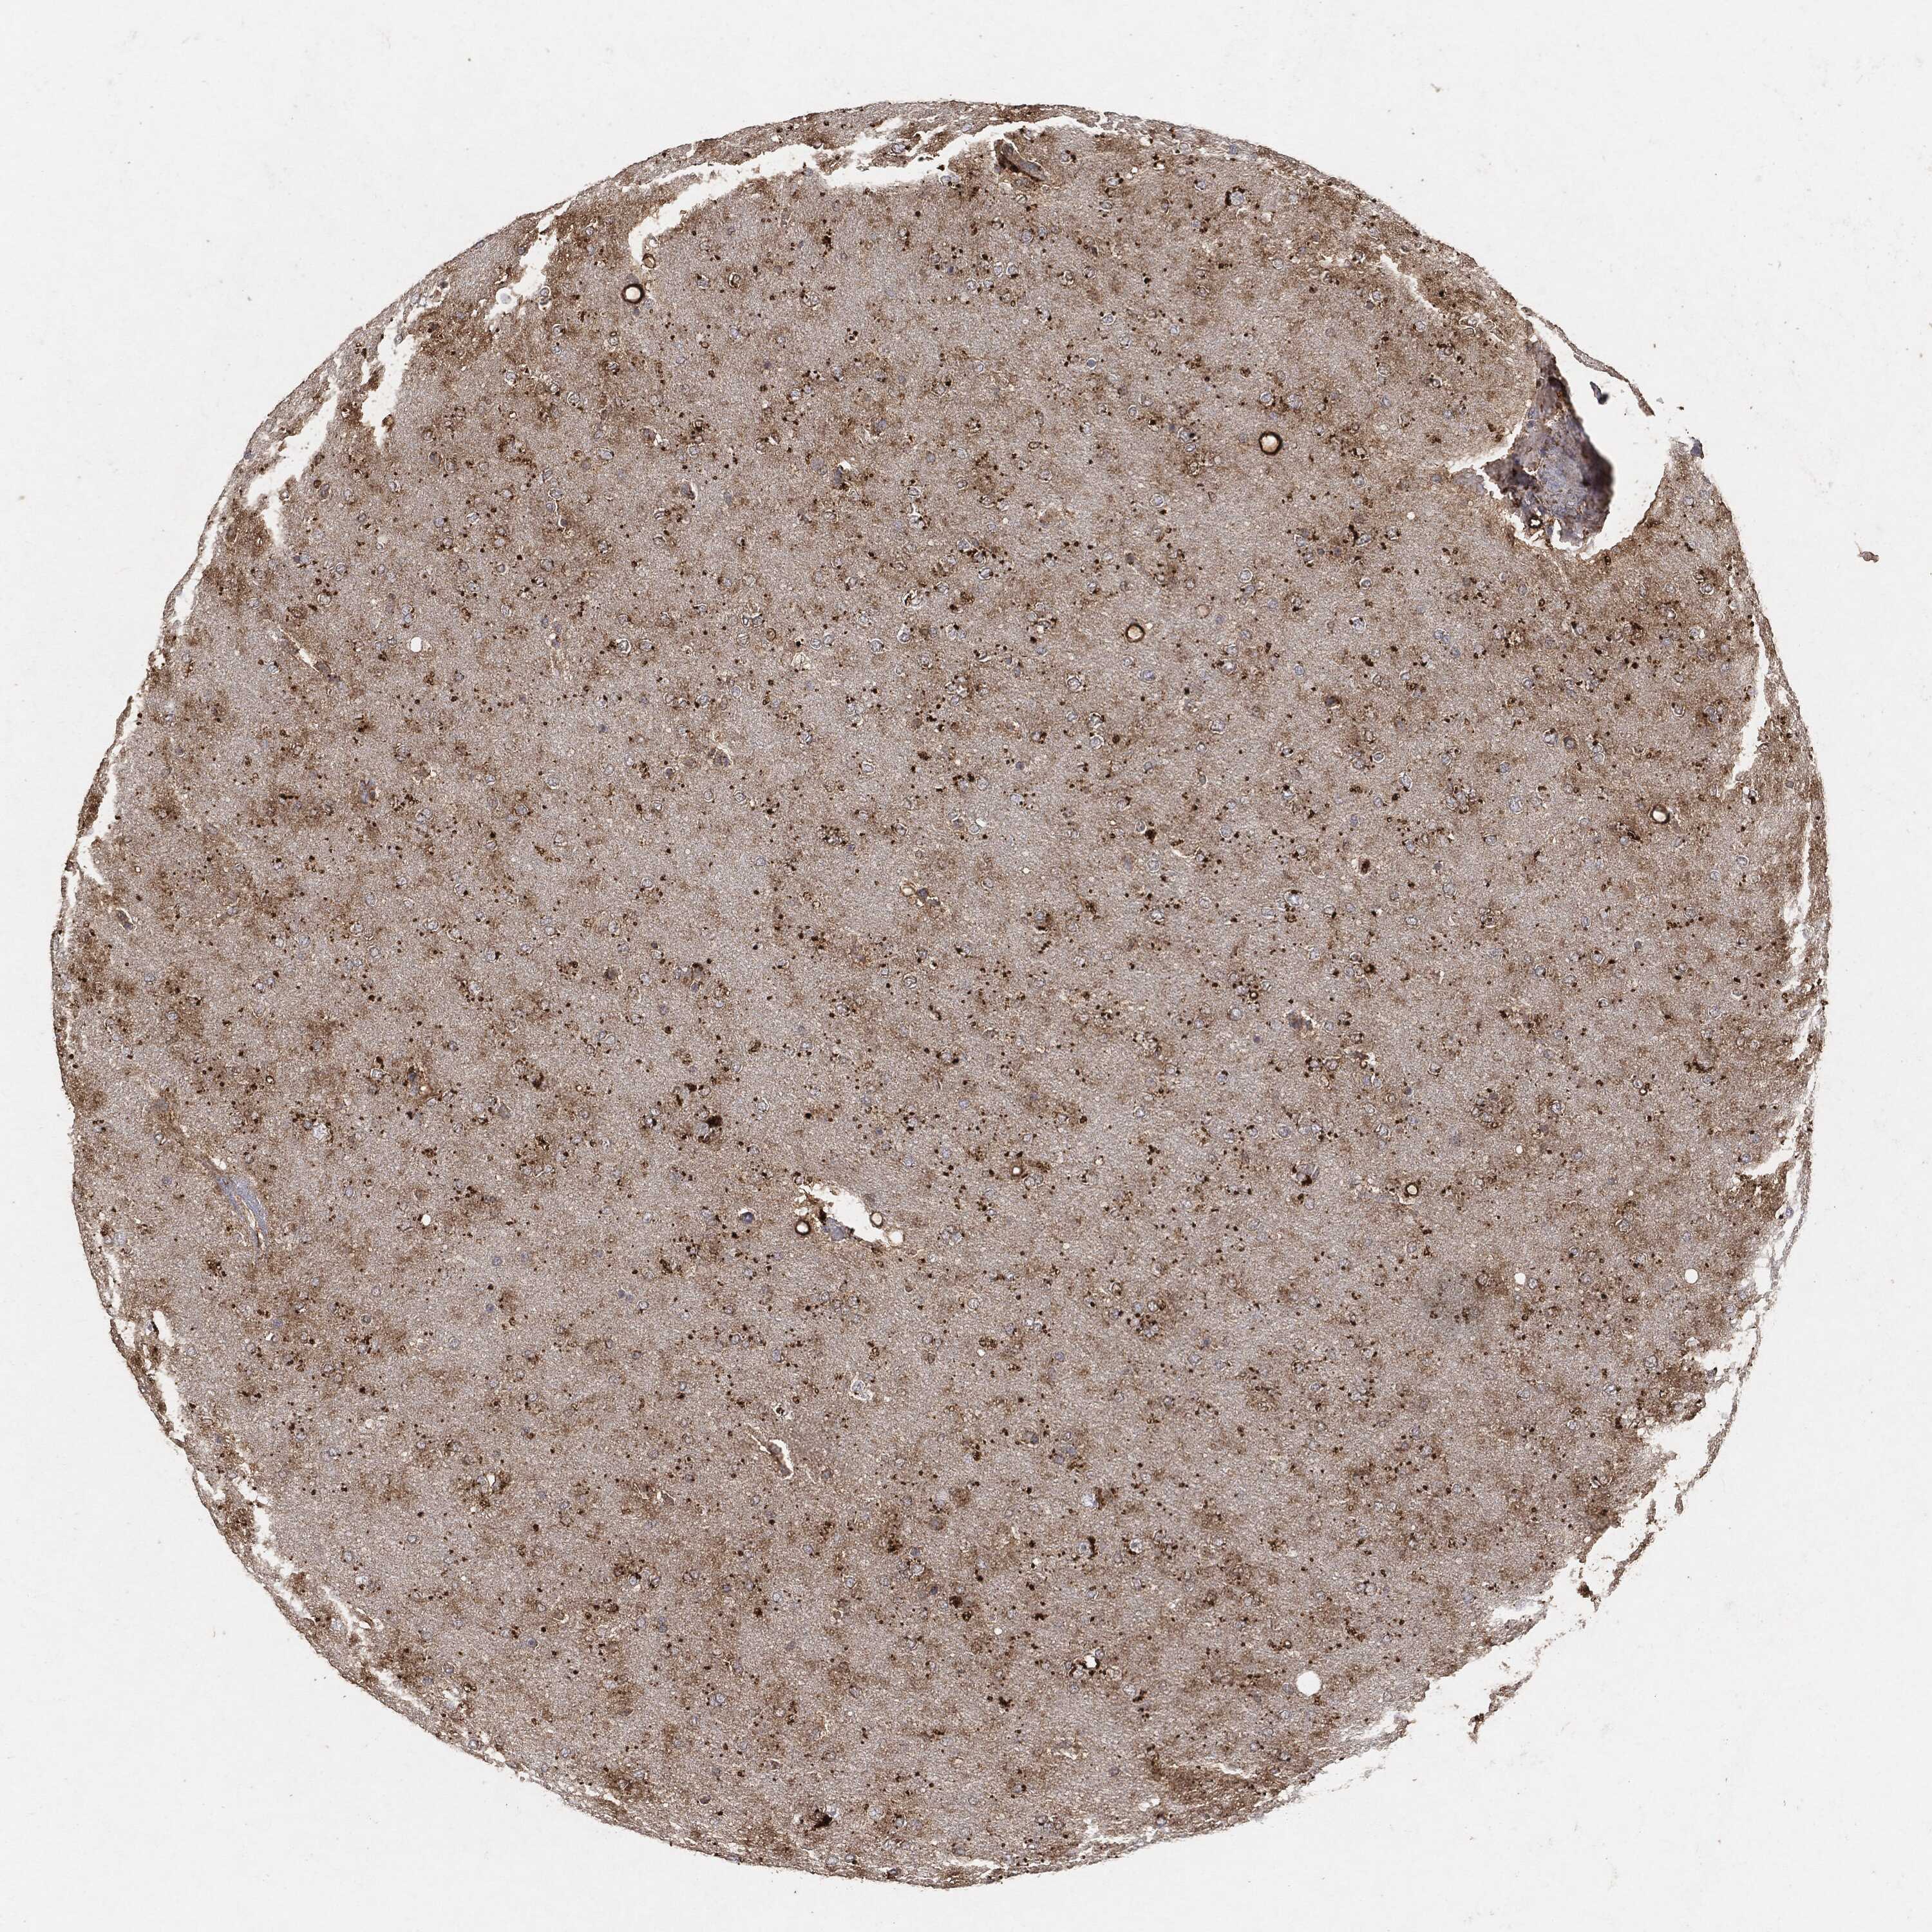

GLIOMA - Protein expressioni

A mouse-over function shows sample information and annotation data. Click on an image to view it in a full screen mode. Samples can be filtered based on level of antibody staining by selecting one or several of the following categories: high, medium, low and not detected. The assay and annotation is described here.

Note that samples used for immunohistochemistry by the Human Protein Atlas do not correspond to samples in the TCGA dataset.

Antibody stainingi

Antibody staining in the annotated cell types in the current human tissue is reported as not detected, low, medium, or high, based on conventional immunohistochemistry profiling in selected tissues. This score is based on the combination of the staining intensity and fraction of stained cells.

Each image is clickable and will lead to virtual microscopy that enables deeper exploration of all samples and also displays staining intensity scores, fraction scores and subcellular localization as well as patient and tissue information for each sample.

Glioma, malignant, High grade

Glioma, malignant, Low grade

Glioma, malignant, NOS